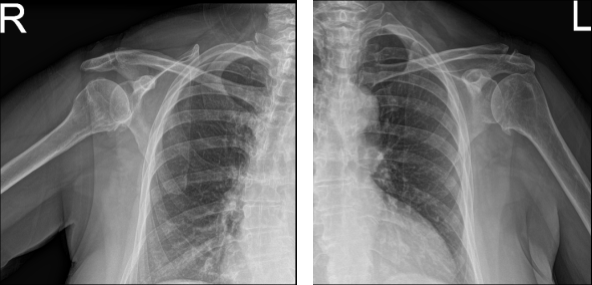

Patient presents today with bilateral shoulder pain. She is 69 year-old, nothing remembers involving in any form of accident. Patient has undergone physical therapy and still experiences the pain. She explains that both shoulders have been hurting for almost 4 years now.

Her pain and restriction of movement are unchanged. She brought her X-ray results today and reviewed them. Her bilateral shoulder showed the impression of mild acromioclavicular and glenohumeral degenerative changes.